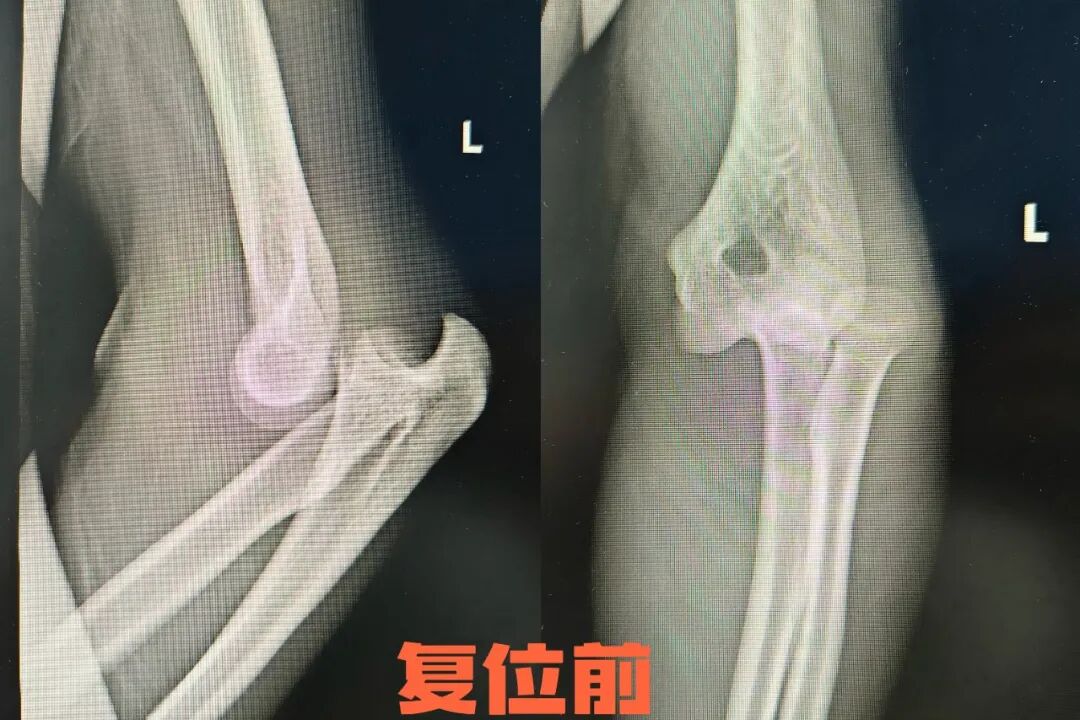

病例一

38岁的樊先生在上班时,不慎摔倒后左肘撑地,当即感到左肘畸形,伴有剧痛、无法弯曲。同事带其到长治二院急诊科就诊。经检查,患者肘部明显畸形,X片检查显示左侧肘关节脱位,位置为肘关节内脱位。急诊科医生采用肘关节手法复位,伴随一声弹响,患者肘关节复位成功,疼痛即刻缓解,并可以小幅度活动肘关节。复位后以高分子支具固定4周,并在康复科功能康复锻炼,左肘活动灵活,恢复了正常生活。